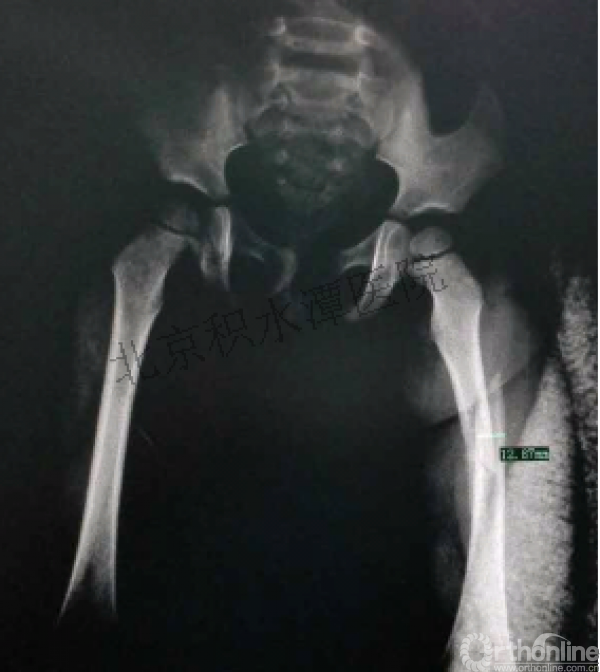

女孩、6岁,股骨干骨折

原始损伤

牵引后4周

伤后18月

没有任何外观和功能障碍!相信每位小儿骨科医生都会有很多类似的病例!除非您不承认或者没有认识到塑形!